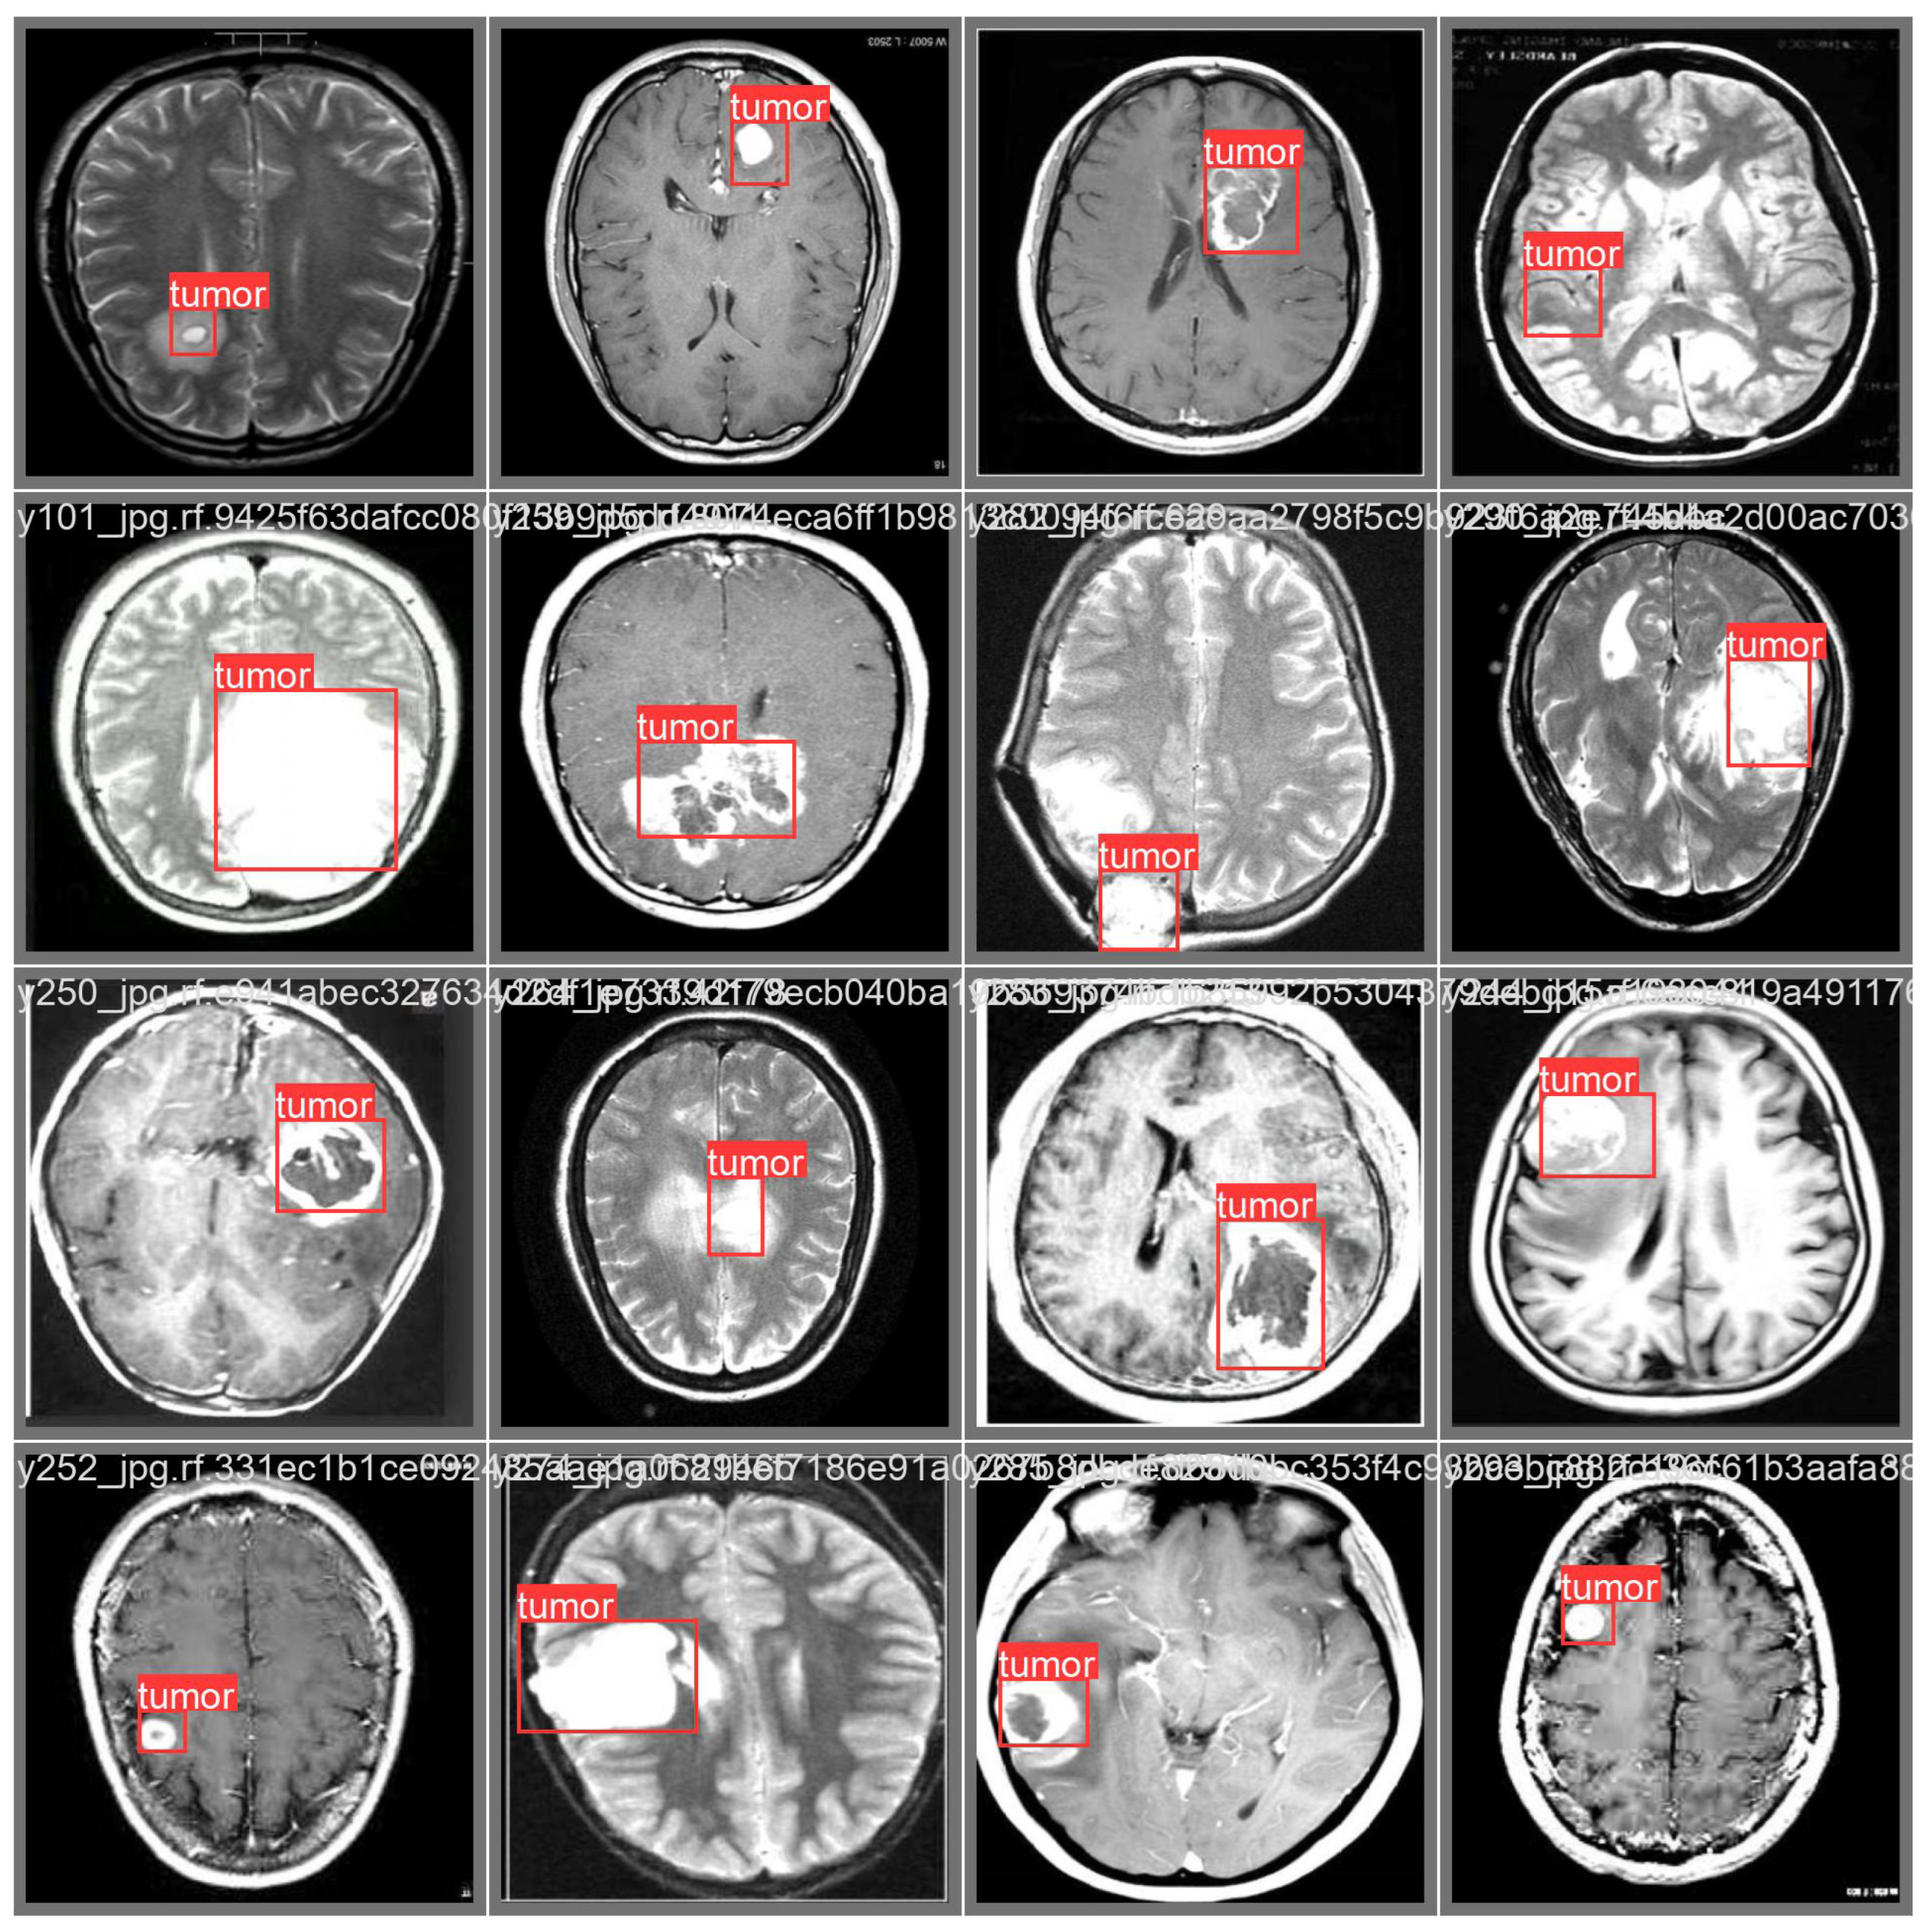

- Classify the image as cancerous;

- Detect the area (i.e., localize) related to brain cancer;

- Assign a probability of the cancer presence.

3.3. Prediction Examples